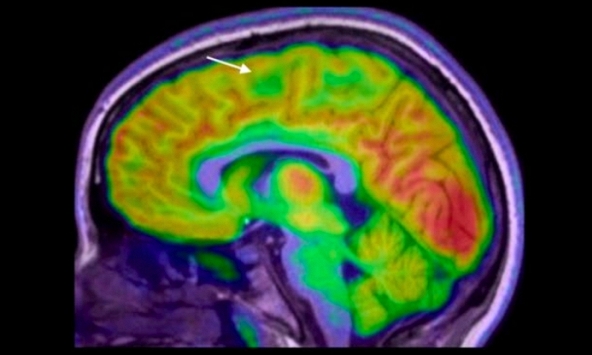

Thực phẩm siêu chế biến có thể âm thầm làm suy giảm khả năng tập trung của não bộ

Một nghiên cứu mới cho thấy việc tiêu thụ thực phẩm siêu chế biến có thể liên quan đến sự suy giảm khả năng tập trung và làm tăng nguy cơ...